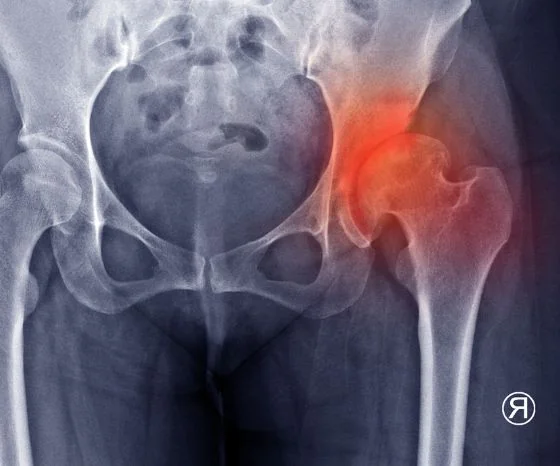

По словам Фелсона и др. (2005) Классическим признаком остеоартрита являются гистологические изменения качества и толщины суставного хряща. Уменьшение суставного хряща приводит к гипертрофии субхондральной кости и образованию остеофитов по краям суставных поверхностей. Еще одно последствие - хроническое воспаление синовиальной ткани. Все эти изменения приводят к неровным суставным поверхностям, увеличению костей, возможному утолщению суставной капсулы и в конечном итоге к гидропсу. Возникающее при этом уменьшение суставного пространства видно на рентгенографических снимках, поэтому мы также говорим о "рентгенологическом остеоартрозе".